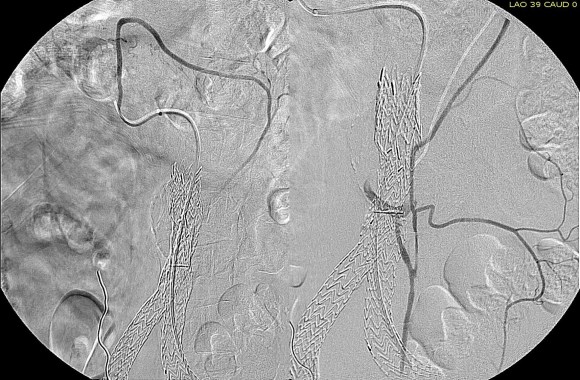

The patient had a successful EVAR or an eccentric infrarenal AAA which in followup grew due to the presence of a type II endoleak from the inferior mesenteric artery. This was seen on the CTA and duplex ultrasound. Planning for assessment and treatment involved analyzing the CTA in centerline, tracking the source of the arterial blood flow into the sac.

The centerline from the SMA into the middle colic artery shows a meandering but patent path via the Arc of Riolan to the left colic artery to the inferior mesenteric artery. In my experience this is straightforward to access selectively from the femoral approach, but it illustrates for the trainees the concept of building up access which I refer to as building the intervention machine.

The first step in the access involves getting stable footing in the SMA. Selective access can be performed with a shaped catheter, and once accessed, a Rosen wire is used to track in a curved long sheath. Parking this sheath in the proximal SMA forms the foundation of this machine. The next step is access into the middle colic artery.

The CTA is particularly helpful in identifying the middle colic on the 3DVR projection. Selection of this is straightforward with a an angle catheter which I place a Tuohy Borst connector. This is the second stage of the machine, because further access with 0.35guage wires and catheters could result in spasm. This second sheath access (the Tuohy turns the catheter into a sheath) of the middle colic allows for selective 0.18 gauge catheters and wires to make the final step to the IMA and the AAA.